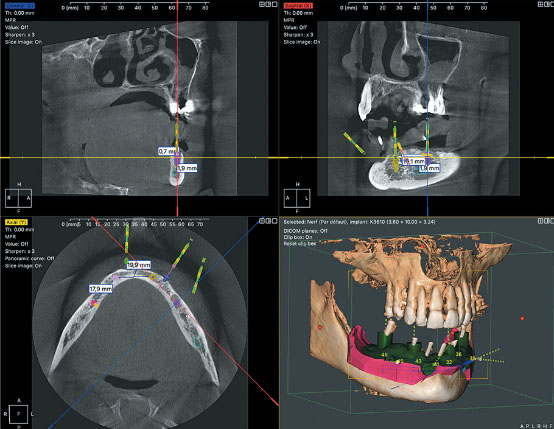

QuickVision 3D Implant planning software

QuickVision 3D is a comprehensive software package that generates panoramic images, cross-sections and bone models based on axial image readings, enabling you to identify the mandibular canal and show the 3D bone model to calculate bone density.

QuickVision 3D allows you to simulate implant placement on 2D and 3D models. To facilitate surgery, the patient's main anatomical features are identified: the exact location of the implant, possible collisions and many other clinical aspects.

Quickvision 3D implant planning software will be your best ally in making prosthetic implant surgery faster, safer and more efficient.

QuickVision 3D interface

QuickVision 3D implant planning QuickVision 3D 3D visualization